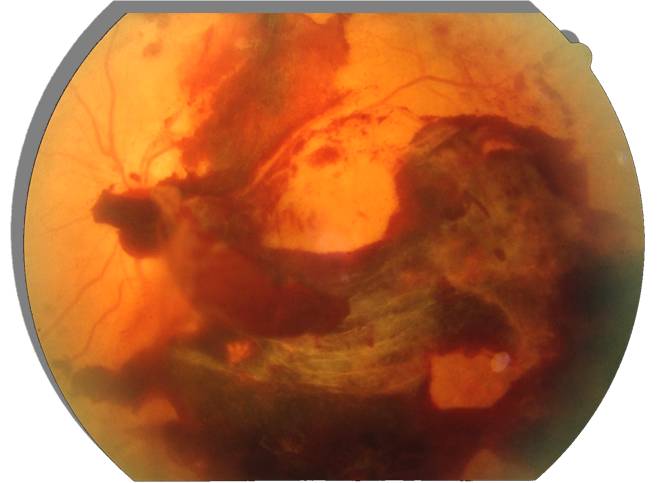

Cuando la diabetes y la hipertensión arterial no son tratadas a tiempo y el paciente no las controla, causan un daño que puede llegar a la ceguera. Cuando, dentro de la clasificación del daño, se alcanza cierto nivel, se requiere la aplicación de láser médico para impedir la pérdida total de la visión. Sin embargo si el paciente es incapaz de controlar su enfermedad crónica; el daño sobre la retina seguirá avanzando inexorablemente.

El desprendimiento de retina es una urgencia oftalmológica y requiere cirugía. Entre los pacientes más afectados se encuentran los miopes, los pacientes que han padecido traumas o cirugías oculares y los afectados por cualquier enfermedad retiniana. Puede sospecharse cuando se comienzan a visualizar manchas volantes o destellos luminosos y sobre todo que se percibe la pérdida abrupta de un sector del campo visual.